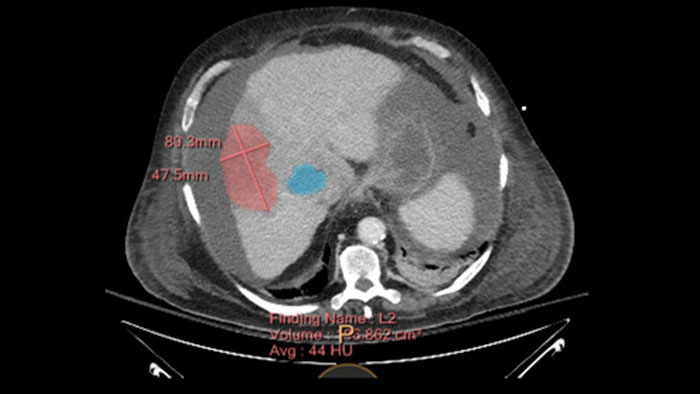

Semi-automatic tumor quantification

This semi-automated 3D (Volumetric) tumor response assessment tool, based on EASL (European Association for the Study of the Liver) criteria incorporates functional information from contrast-enhanced scans.